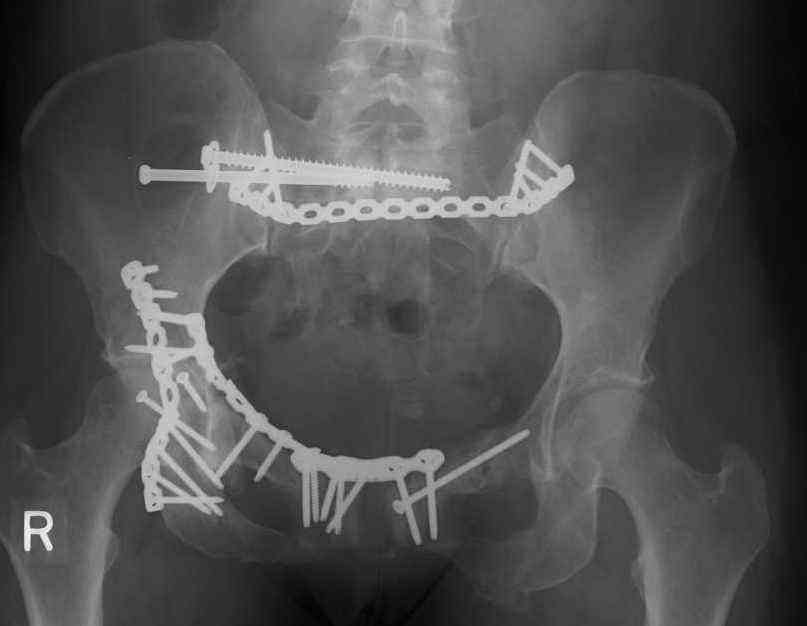

This is a 48 yo non-smoking female s/p MCC 10 months ago. I do not have the initial injury films. She underwent ORIF as shown on attached file.

She is having continued pain in low back/sacral region. Worse with sitting and prolonged walking. Has had pain since surgery. All of her wounds have healed uneventfully. Also has right hip pain laterally. No groin pain. Not aggravated with ROM of the hip. Infection work-up has been negative.

Any thoughts on the broken plate on the pelvic brim and the non-union on the anterior column. Doesn't seem like she's have pain from there.

Suggestions on treatment of sacral nonunion.